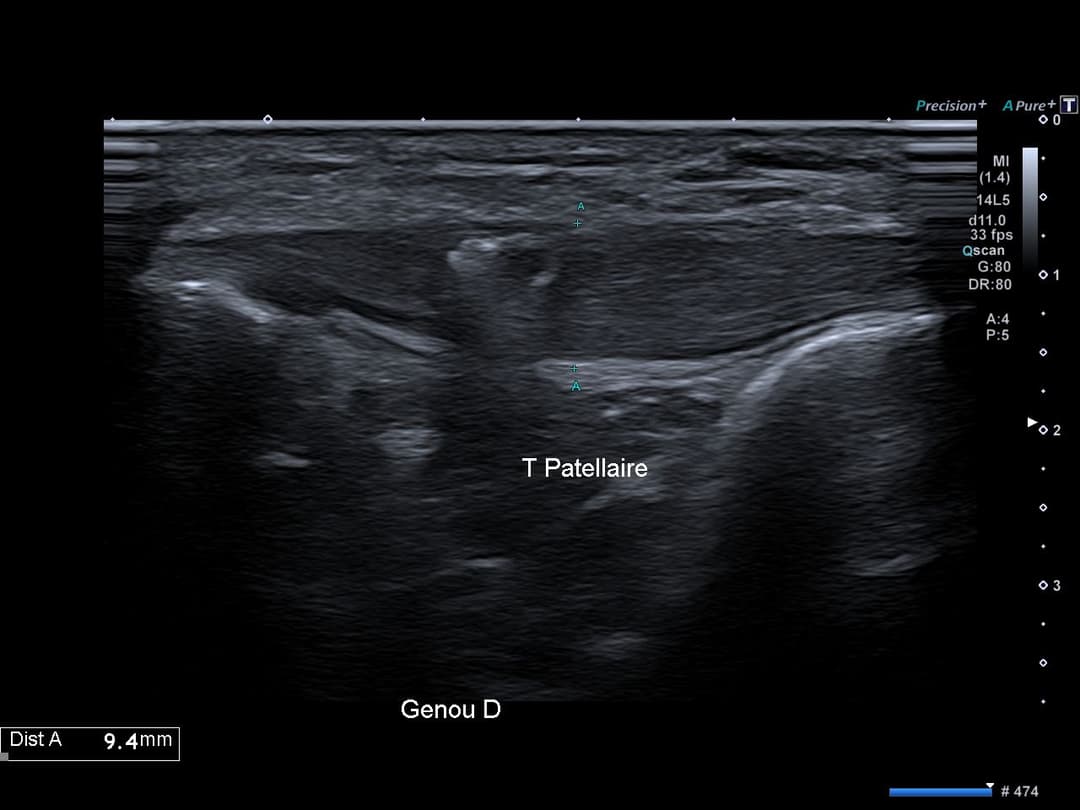

Tendon patellaire présentant un épaississement global et fusiforme de sa portion corporéal, mesurant jusqu’à 8 mm d’épaisseur à droite contre 4 mm à gauche, avec légère perte de son architecture fibrillaire sans fissuration.